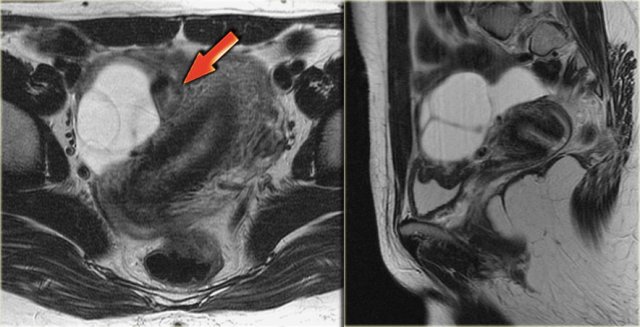

Corpus luteum cyst at MRI: an axial T2-weighted image demonstrating an involuting corpus luteum cyst (arrow).

This is a normal finding.

The right ovary is also normal.

Axial and sagittal T2W images from the same patient.

The right ovary contains multiple simple T2 bright cysts with thin borders and no solid components.

On the axial image there is one lesion, that is dark on T2, i.e. a complex cyst (arrow).

There is a small amount of ascites around the right ovary, but not enough to raise concern of a possible neoplasm.

On the T1-weighted image without fatsat the complex cyst is bright, indicating either fat or blood content.

On the T1-weighted image with fatsat the lesion remains bright, ruling out a fatty lesion.

After the administration of Gd there is no enhancement, confirming that this is a hemorrhagic ovarian cyst.